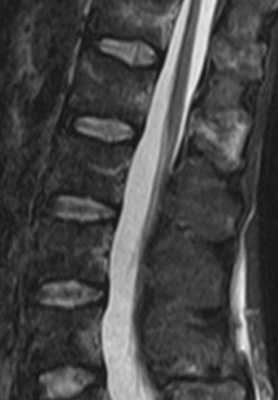

(Слева) Т1-ВИ, сагиттальный срез: признаки дегенеративного сколиоза, выраженного многоуровневого фораминального стеноза и спондилолиза на уровне L5-S1. На каждом из уровней имеет место дегенеративное поражение межпозвонковых дисков со значительным снижением их высоты и ретролистезом.

(Справа) Т2-ВИ: у пациента с дегенеративным сколиозом отмечается усиление Т2-сигнала межпозвонковых дисков на различных уровнях, что является проявлением дегенерации дисков, а не инфекционного процесса. (Слева) КТ с КУ, сагиттальный -срез: типичный случай многоуровневого спондилеза шейного отдела позвоночника с выраженным стенозированием спинномозгового канала, снижением высоты межпозвонковых дисков и эбурнеацией замыкательных пластинок от уровня С2-СЗ до С5-С6. Также здесь видны признаки кальцификации межпозвонковых дисков и задней продольной связки.